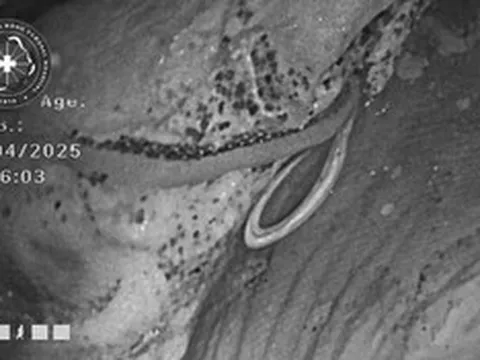

Người đàn ông 62 tuổi tử vong dù chăm tập thể dục, bác sĩ chỉ ra sai lầm

Người đàn ông 62 tuổi tử vong vì suy thận giai đoạn cuối. Ảnh minh họa.